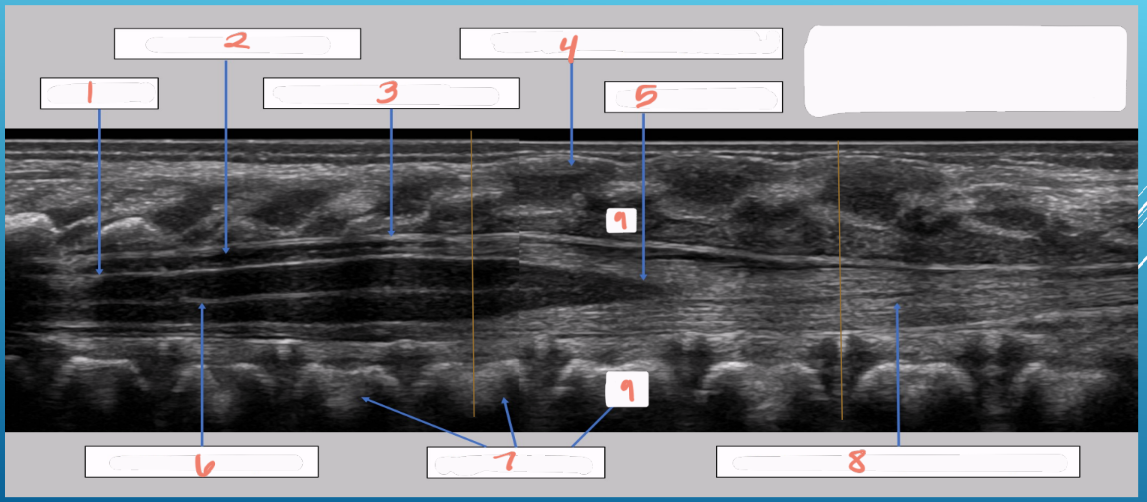

1

spinal cord

2

subarachnoid space

3

arachnoid and dura mater

4

cartilaginous spinous process

5

conus medullaris

6

central echo complex in hypoechoic spinal cord

7

vertebral bodies

8

nerve roots forming the cauda equina